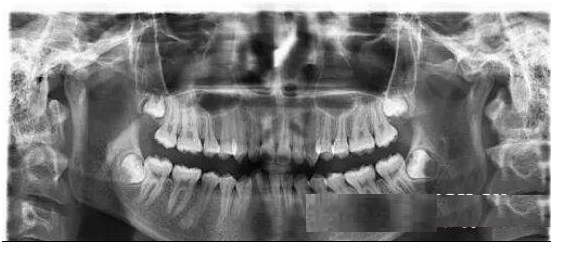

智齿俗称“尽头牙”,在人类的恒牙列中共有32颗牙,而最后萌出的4颗牙齿在最后方,一般在16-25岁成长期萌出,极少人会在四五十岁才开始萌出。所以有“智齿”之称。“也不是所有人都长4颗智齿,就医院目前接诊的情况看,有只长一颗、两颗的,大部分是长的4颗,也有少数人是不长‘智齿’的,也有极少数长了5颗智齿。绝大部分智齿都要拔,只有三种情况不需要拔智齿。第一:智齿完全长出来了,萌出在口腔正常位置,并且与对面的牙齿有正常咬合关系,与旁边牙齿有正常邻接关系。保证牙齿不容易嵌塞食物,容易清洁;第二:智齿完全没有长出来的,嘴巴里看不到,口腔内没有任何症状,通过拍牙片可以看到,但是硬拔出来创伤比较大;第三:智齿作为第三磨牙,如果前面第一、第二磨牙坏了,可以通过正畸等方式用智齿替代第一、第二磨牙;就可以考虑先不拔。龋坏:也就是大家熟悉的蛀牙,如果智齿发生蛀牙,除了很简单的咬合面不深的蛀牙可以补,那些邻接面蛀牙,以及蛀得很深,甚至需要根管治疗的,建议拔除,治疗保留意义不大。

侵犯邻牙:通常智齿萌发的空间不足,而会倒在第二磨牙上,因而造成第二磨牙清洁不易,早期通常患者不自知,而由牙医以检查得知。后期可出现龋坏,牙髓炎、根尖周炎而发生自发痛,甚至是牙槽骨、牙根部分吸收的现象。

空间不足:在人类的演化史上,牙弓越来越小,但牙齿的数量和体积不变,因此最后萌出的牙出现萌出空间不足的情况是很常见的。在萌出的时候反复发炎,感觉到肿胀、疼痛,导致智齿冠周炎、颌面部间隙感染等,需要炎症控制后拔除。很多人就是因为不能忍受这种疼痛感,而决定拔掉智齿。

清洁不易:由于空间不足的关系,智齿常长得歪七扭八,因此常造成清洁牙齿的困难,以致发生蛀牙现象。

没有对咬牙:不是每个人四个智齿都会长齐的。所以,智齿的对面,如果没有相抗衡的智齿来对咬的话,有时会发生智齿过度伸长,进而影响咬合,影响颞下颌关节等。

阻生齿:这一种类型的牙齿,通常没有完全萌出,大部分埋在牙槽骨里面,如果会导致疼痛或是诊断会有病灶发生的时候,就需要拔除。

某医科大学附属口腔医院口腔颌面外科门诊开展微创拔牙、心电监护拔牙、口腔颌面部门诊手术等治疗。现有医护人员20余名,其中教授1名、副教授3名,博士4名、硕士7名;留学归国人员4名。拥有SAT计算机控制无痛麻醉仪,法国赛特力Piezotome超声骨刀,心电监护仪等先进医疗设备。